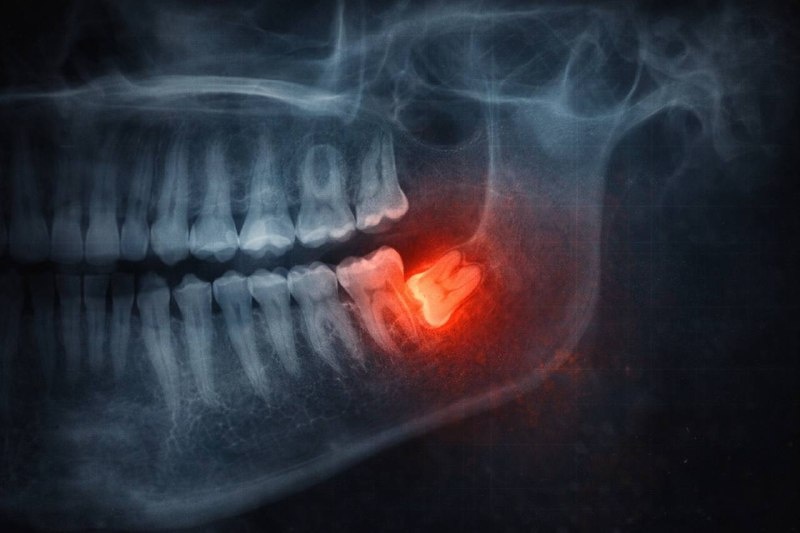

Факт 3: Почему их всё-таки удаляют

Проблемы начинаются, когда зуб мудрости:

растёт под углом, частично скрыт под десной, давит на соседний зуб, плохо доступен для гигиены.

В таких случаях риск воспалений, кариеса и смещения прикуса действительно выше,

В таких случаях риск воспалений, кариеса и смещения прикуса действительно выше, и удаление оправдано.